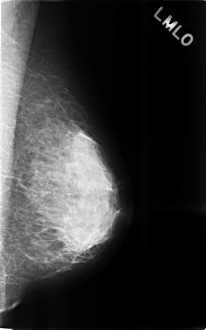

C_0284_1.LEFT_MLO

LEFT_MLO LINES 4608 PIXELS_PER_LINE 2872 BITS_PER_PIXEL 12 RESOLUTION 50 NON_OVERLAY